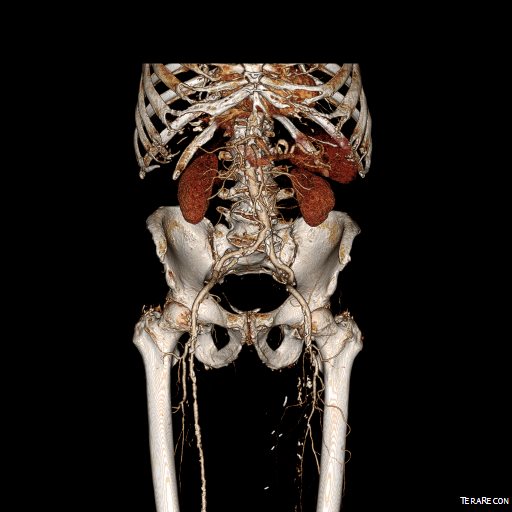

The patient is an 70 year old man referred for evaluation of claudication that occurred at under a block of walking. He reported no rest pain or tissue loss. He smoked heavily up to a pack a day, with congestive heart failure with an ejection fraction of 40%, prior history of myocardial infarction treated with PTCA, and pacemaker, and moderate dyspnea on exertion.

On examination, patient had a flaccid abdomen through which the AAA could be palpated, and he had no palpable femoral artery pulse bilaterally, nor anything below. He had a cardiac murmur and moderate bilateral edema. Preoperative risk evaluation placed him in the high risk category because of his heart failure, coronary artery disease, and his mild to moderate pulmonary disease.

CTA (pictured above and below) showed a 5.1cm infrarenal AAA with an hourglass shaped neck with moderate atherosclerosis in the neck, an occluded left common iliac artery with external iliac artery reconstitution via internal iliac artery collaterals, and a right external iliac artery occlusion with common femoral artery reconstitution. There was calcified right common femoral artery plaque.

Treatment options included open surgical aortobifemoral bypass with exclusion of the AAA, total endovascular repair with some form of endo-conduit revascularization of the occluded segments of iliac artery, or a hybrid repair.